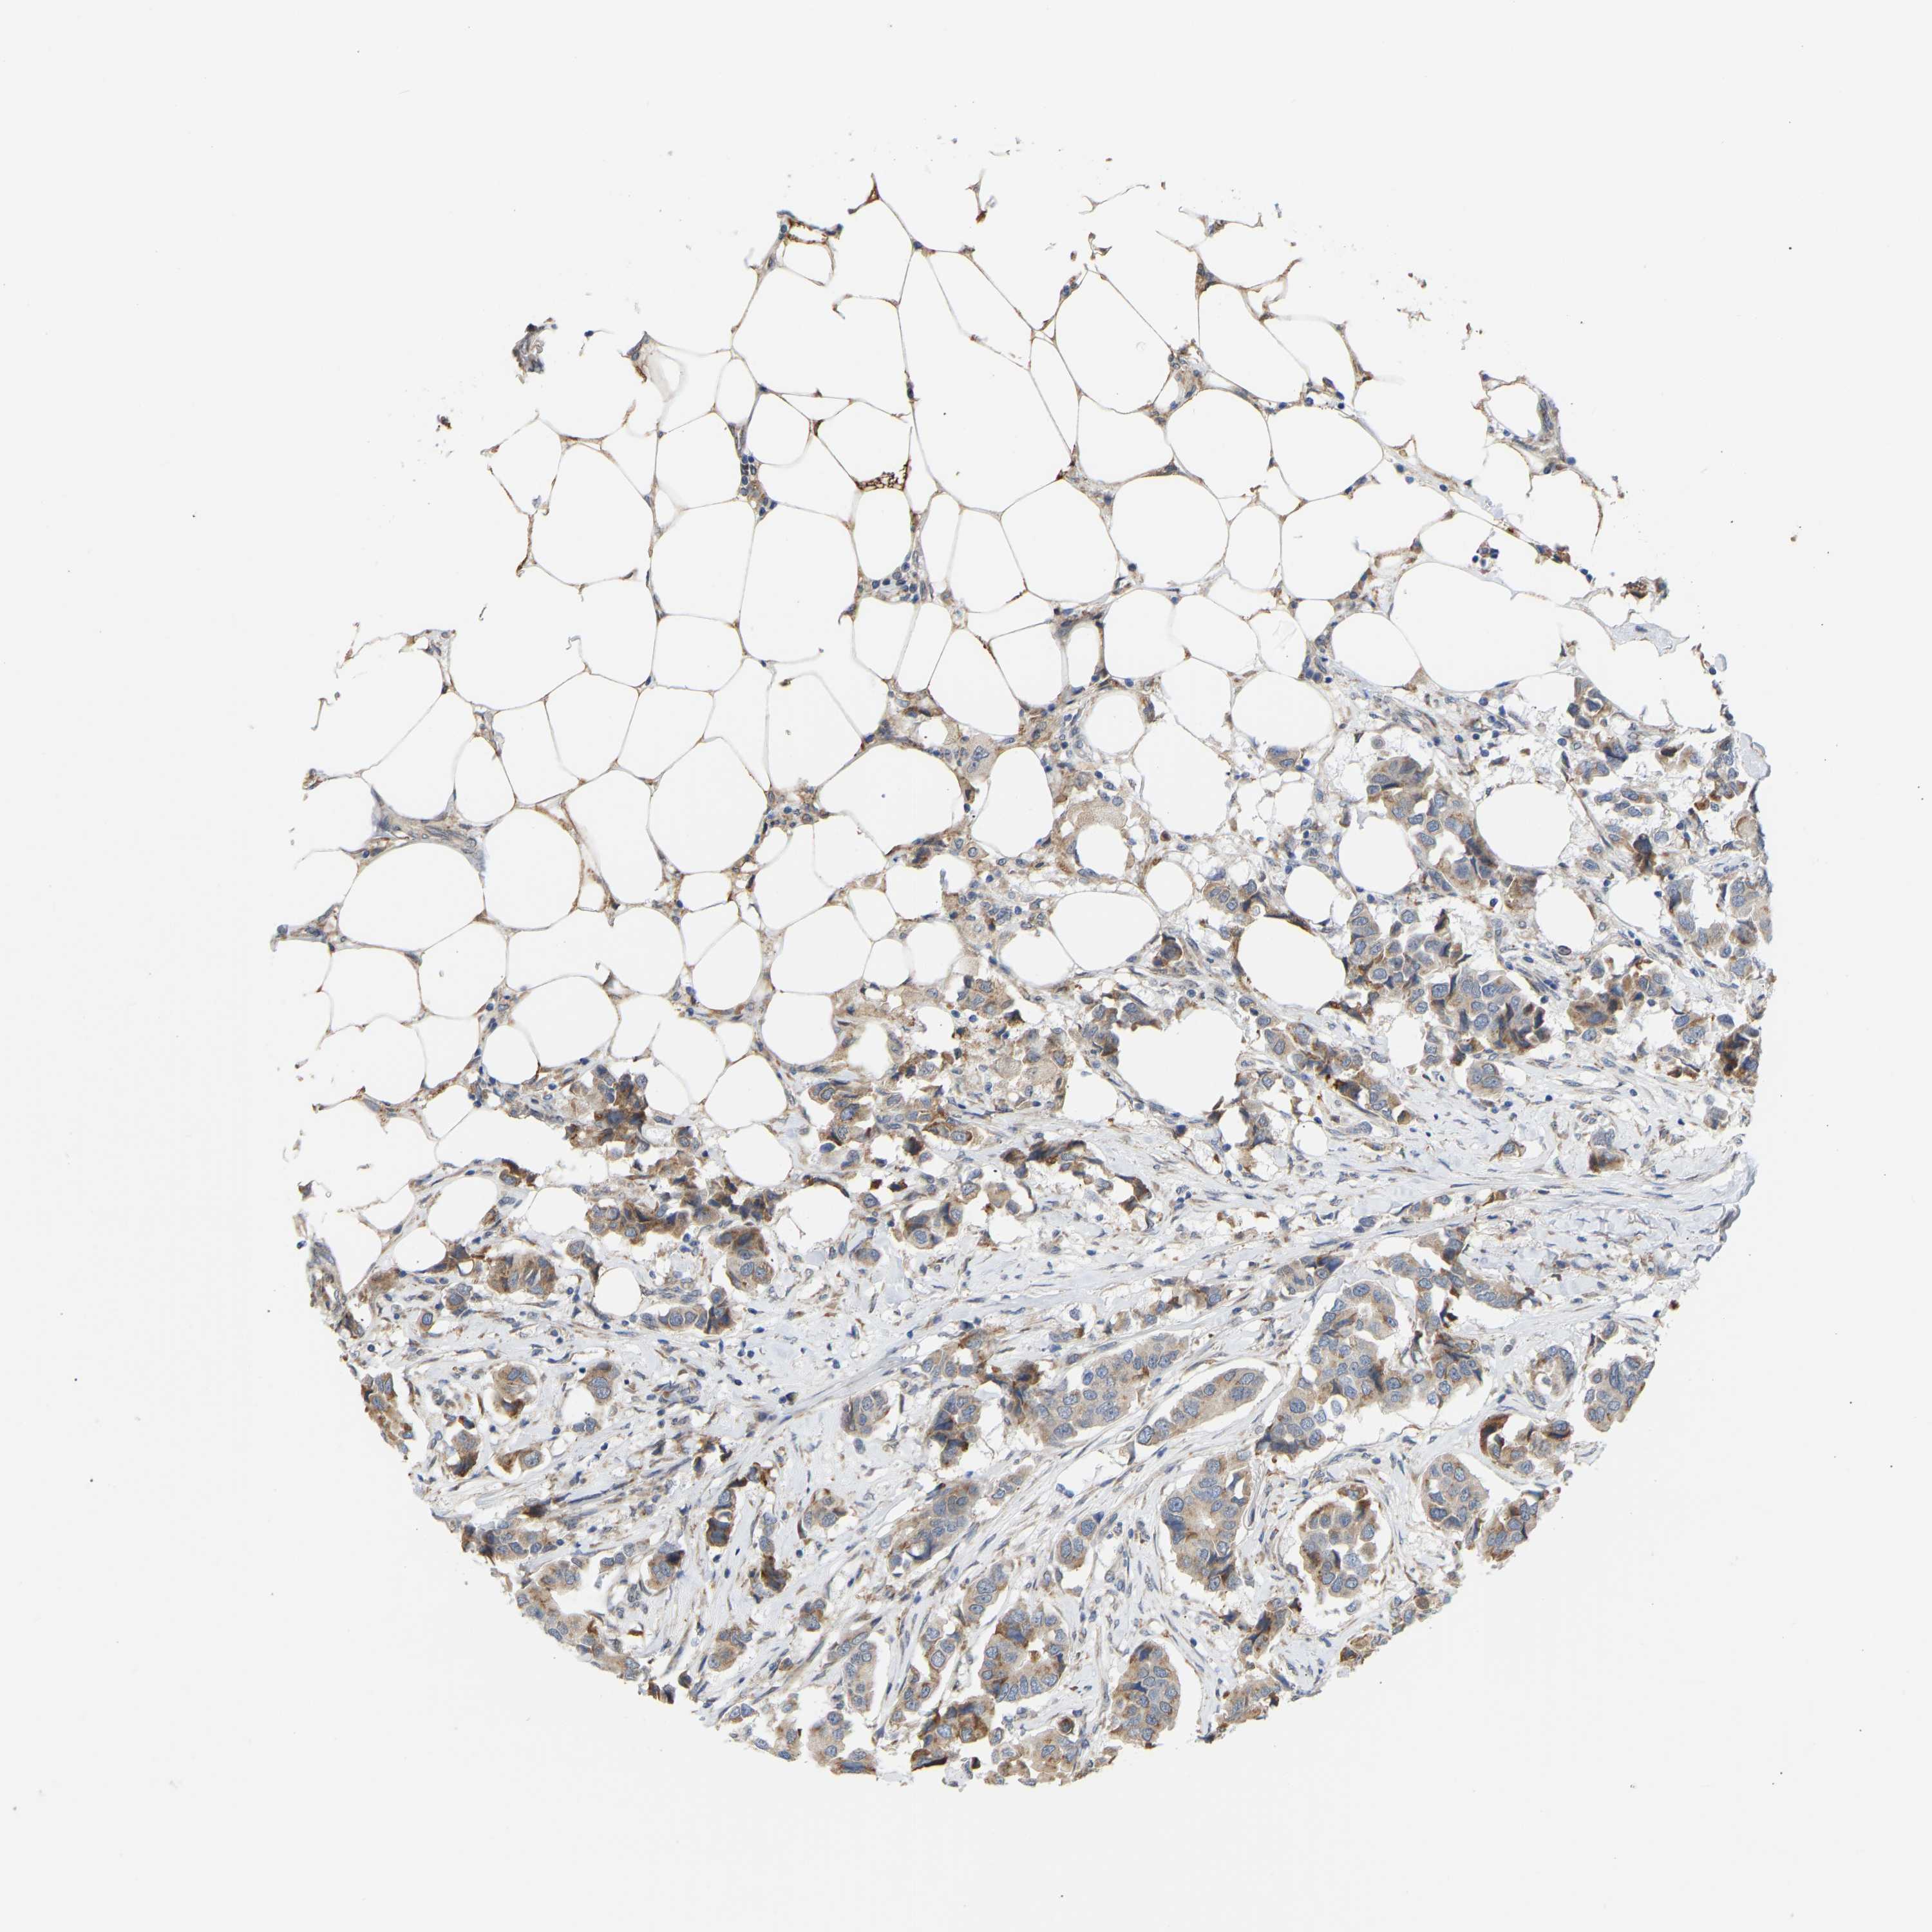

CANCER BREAST CANCER Show tissue menu

BRCA TCGA BRCA VALIDATION PROTEIN EXPRESSION